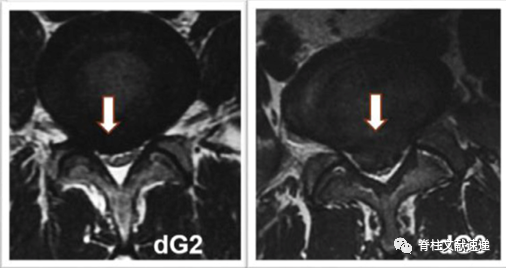

1级:椎间盘与神经根接触但未受压(nG1),或硬膜囊受压<椎管的1/3(dG1);

2级:神经根受压移位(nG2),或硬膜囊受压>1/3而<1/2(dG2)。

行髓核摘除术时,若无症状椎间盘突出为G2程度的神经根受压,再手术率较高;若为G2程度的硬膜囊受压,再手术率无明显提高。这对初次手术时髓核摘除术减压节段的选择提供了一定参考。